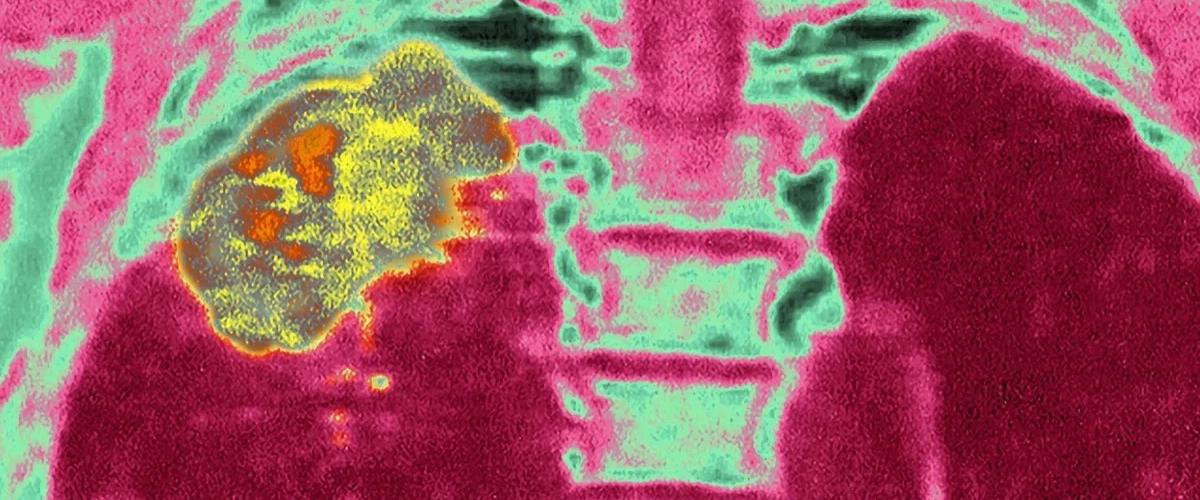

Первые эксперименты на макаках с раком печени показали, что в группе контря все животные умерли в среднем через четыре месяца после лечения. На фоне лечения все животные прожили более шести месяцев. После этих результатов стартовали пилотные клинические исследования с участием 23 добровольцев с различными типами опухолей: печени, пищевода, прямой кишки, яичников, легких, груди, кожи, шейки матки и т. д. Все опухоли были резистентны к стандартным методам лечения рака.

Через два года у пяти добровольцев опухоли перестали расти. У двоих они уменьшились, но не исчезли полностью. У нескольких человек после заметных улучшений снова наблюдался рост рака. Наконец, некоторые вообще не получили пользы от терапии. Авторы считают, что отсутствие пользы могло быть вызвано сильной запущенностью рака. В дальнейших исследованиях терапию протестируют у пациентов на второй и третьей стадии.